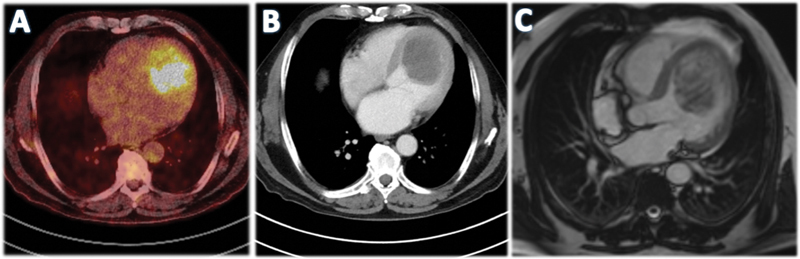

A 71-year-old man with dilated cardiomyopathy without clinical complaints revealed a suspicious finding in checkup. After a multimodality cardiac imaging, the suspicion of a malignant primary cardiac tumor in the left ventricle was substantiated and the patient underwent minimally-invasive cardiac surgery for tumor resection. Postoperative chemotherapy with multiple cycles of liposomal doxorubicin was established and supported by proton beam radiotherapy. Two-year follow-up revealed no disease recurrence.

Abstract Image